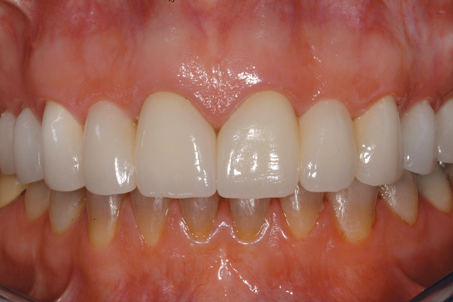

(13.) Close-up retracted 2-month postoperative view of the final fixed partial dentures spanning teeth Nos. 6 through 8 and teeth Nos. 9 through 11, along with replacement crowns for the other restored maxillary teeth.

Figure 13

A patient presented with two defective 3-unit fixed partial dentures spanning teeth Nos. 6 through 8 and teeth Nos. 9 through 11 (Figure 7). The defective fixed partial dentures were removed (Figure 8), an impression was made, and traditional provisional fixed partial dentures without ovate pontics were placed. After the impression was sent to the laboratory, the lab technician prepared ovate pontic sites on the stone cast (Figure 9) and fabricated the new definitive bridges. On the day of insertion, the provisional fixed partial dentures were removed (Figure 10), ovate pontic sites were prepared using a teardrop-shaped diamond bur (Figure 11), and the sites were sounded to confirm that there was at least 2 mm from the base of the pontic site to the alveolar bone (Figure 12). The fixed partial dentures were cemented, and the postoperative healing was uneventful (Figure 13).

Although the use of implant-supported crowns in the anterior region has become more predictable, the use of pontics in conjunction with both natural teeth and implants is still common in restorative dentistry. When an ovate pontic design is selected and the site is properly prepared to meet prosthetic biologic width requirements, superior esthetics can be achieved with traditional fixed partial dentures.